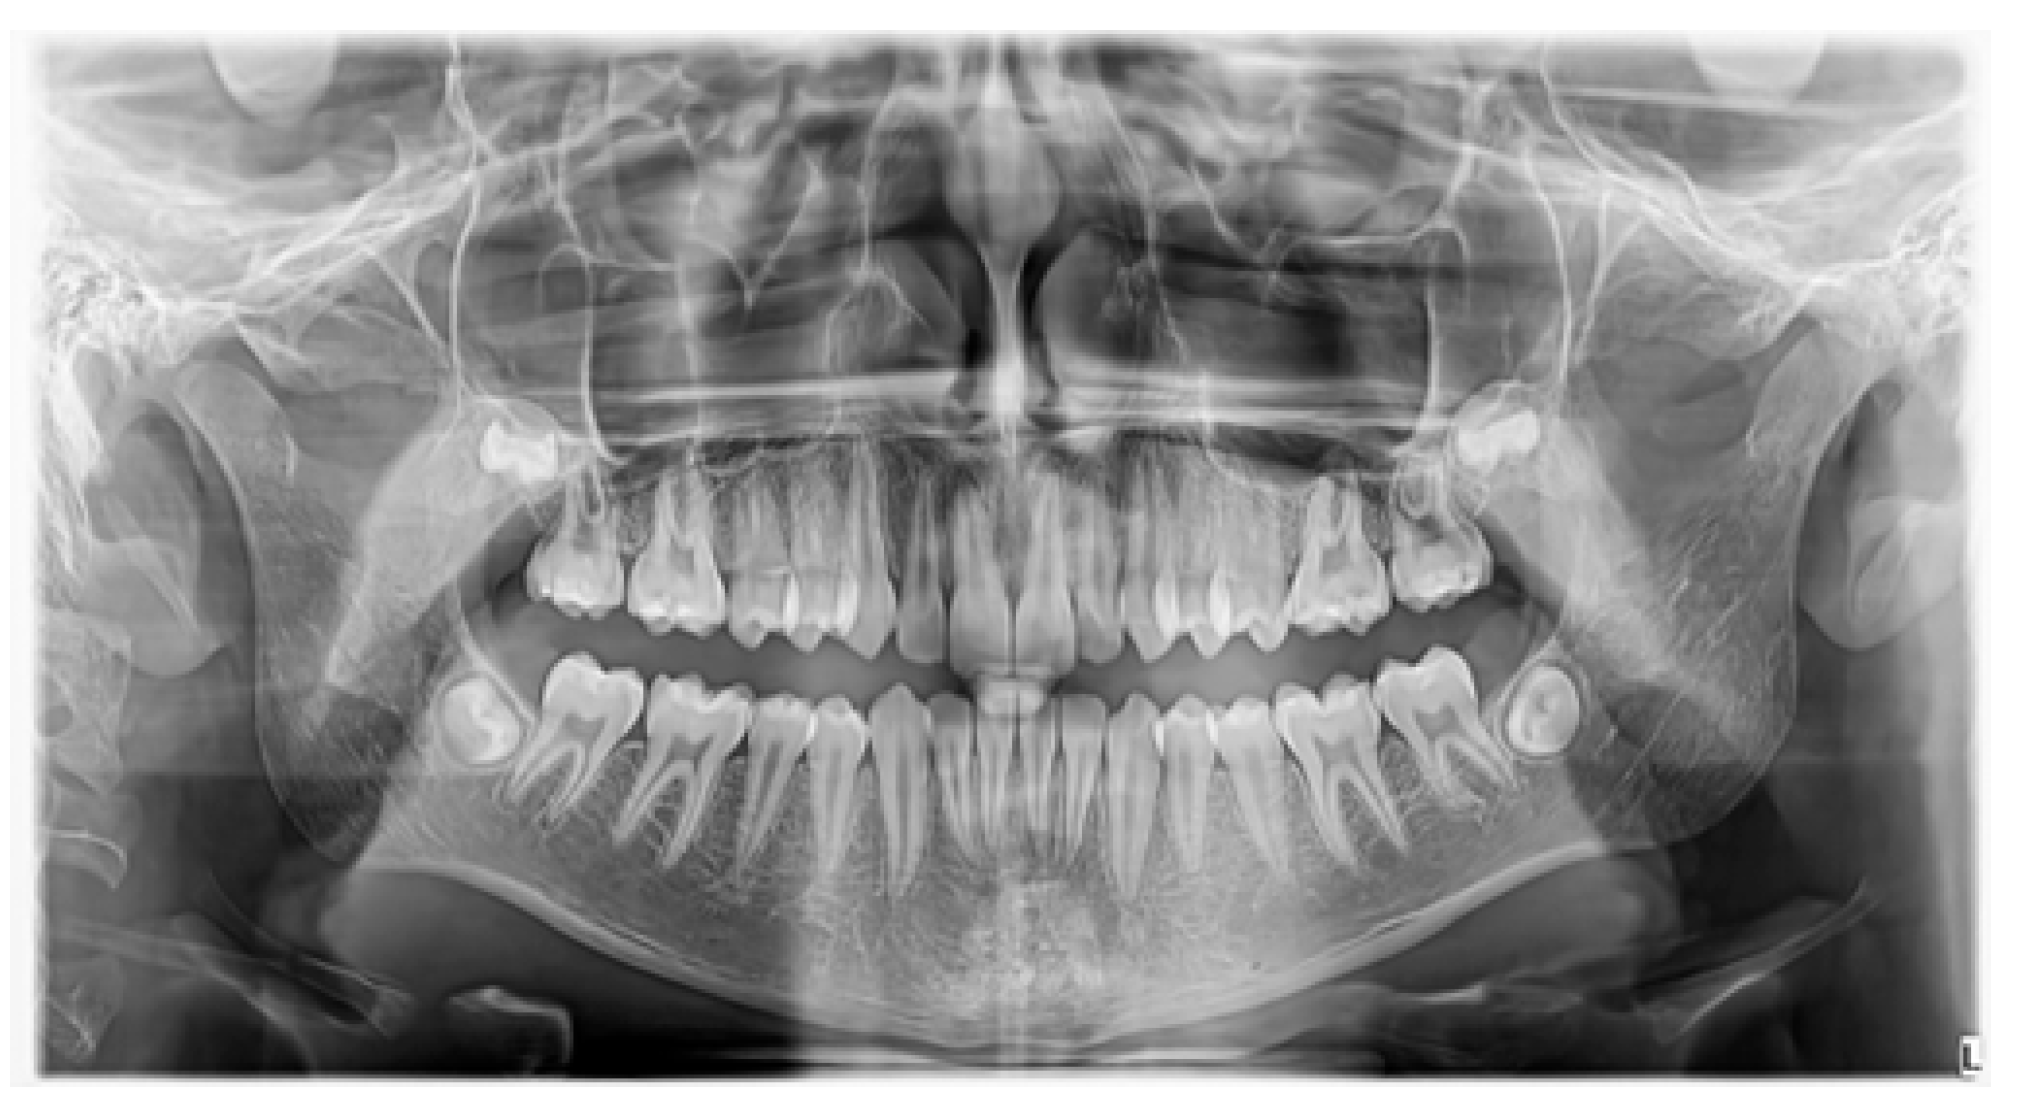

3.1. Case 1 (Figure 3, Figure 4 and Figure 5)

| Conventional radiography (OPG, occlusal, periapical, lateral cephalometric radiographs) | In the case of conventional 2D radiographs, mainly OPGs, the structures outside the focal area may be covered by other structures and cannot be visualized. Also, precise localization in relation to other anatomical elements or neighboring teeth will require the use of an additional occlusal radiograph. |

| CBCT | A 3D radiographic imaging method is an excellent method of evaluation and diagnosis. It has a fundamental role in the precise localization of the mesiodens and a connection with the neighboring anatomical structures and teeth. Thus, it has an important role in choosing the appropriate surgical procedure. |